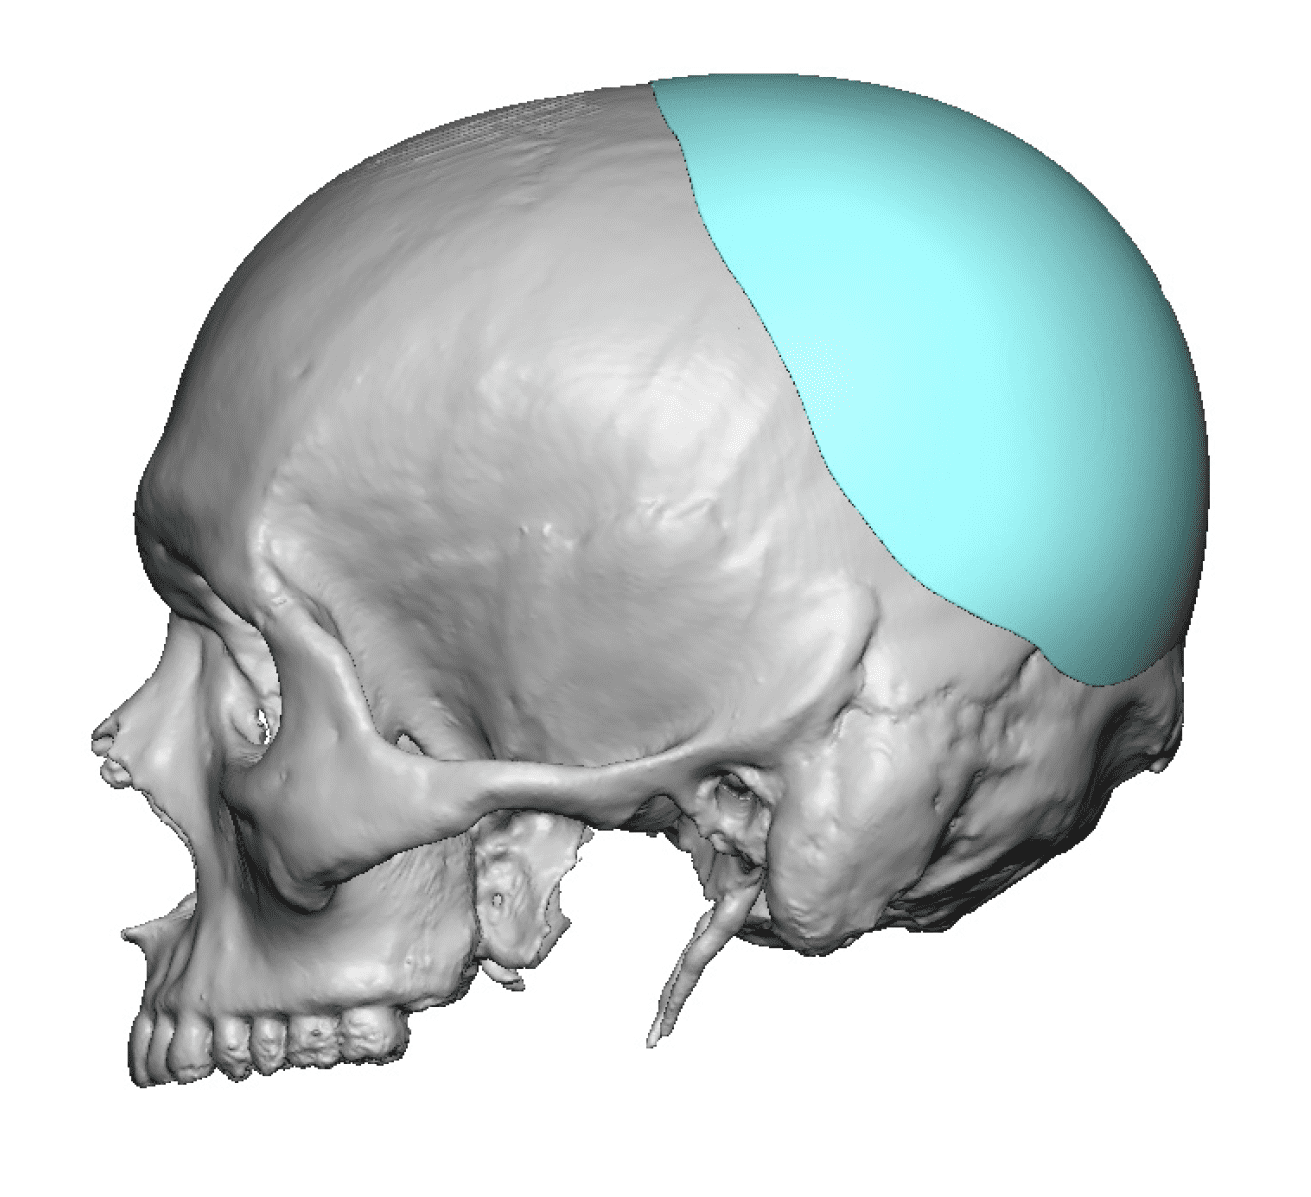

Desire for further skull augmentation after a primary skull implant.

Five years after an initial custom skull implant placement a new custom skull implant that increased the volume by 35% was placed.

Desire for further skull augmentation after a primary skull implant.

Five years after an initial custom skull implant placement a new custom skull implant that increased the volume by 35% was placed.